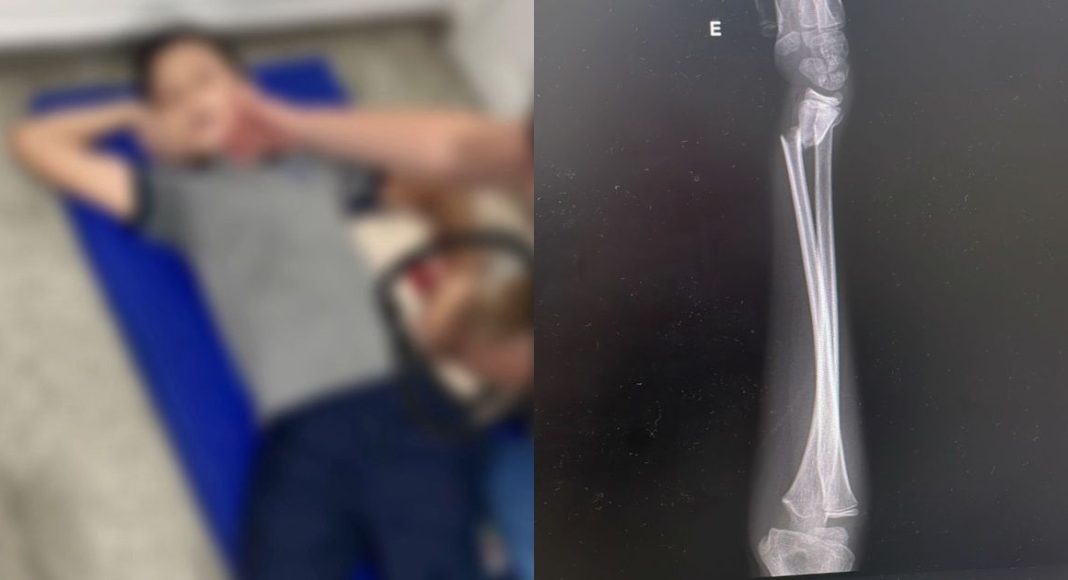

Uma mãe denunciou uma suposta negligência da Escola Municipal Enfermeira Hilda Anna Krisch, no bairro Jardim Iririú, em Joinville, após o filho, de 9 anos, sofrer uma queda e quebrar o braço esquerdo durante a aula de educação física. O acidente aconteceu na segunda-feira, 17.

Segundo a mãe, Karina Soares Honorato, o menino participava de uma partida de queimada quando tropeçou ao correr de costas e cair, apoiando o braço no chão. A queda teria acontecido por volta das 15h20. A direção da escola enviou uma mensagem informando que o aluno havia se machucado durante a atividade.

A criança de 9 anos passou por cirurgia e está internada no Hospital Infantil de Joinville. Os pais do estudante avaliam fazer um boletim de ocorrência contra a Escola Municipal Enfermeira Hilda Anna Krisch.